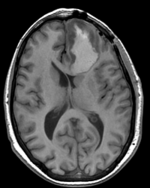

this is the fixed T1 reference image. All images are aligned into this space this is the FLAIR scan, to be registered with the T1 lleft this is the T1Gd image, serves as reference to which all others are aligned lleft this is the DTI tensor image, to be registered with the T1

fixed image/target

T1

• reference/fixed : T1 axial, 0.5 x 0.5 x 1 , 512 x 512 x 176